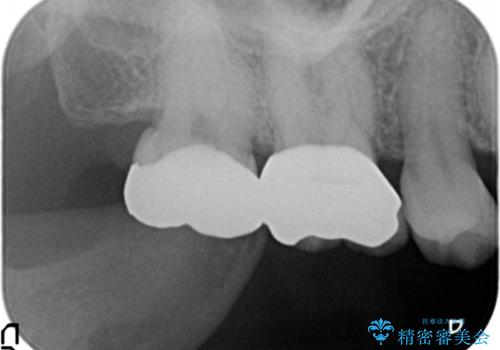

- 笑った時に目立つ銀歯を改善したいとのことで来院されました。

保険適応の銀歯を除去し虫歯を取ったのち、ジルコニアクラウンで置き換えていきます。